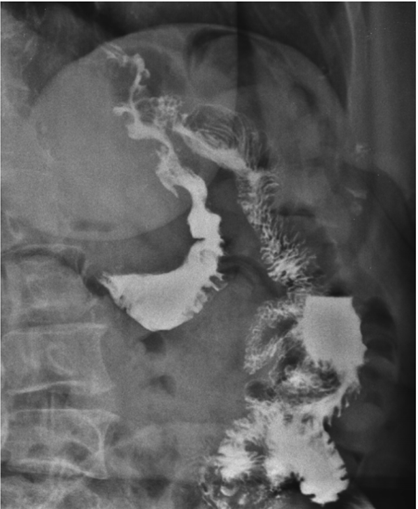

Mulher de 55 anos, submetida à cirurgia bariátrica há 6 meses sob técnica de bypass gástrico em Y de Roux, queixa-se de desconforto epigástrico e de dores intermitentes no abdome superior há 3 meses, sendo solicitado pelo médico cirurgião exame contrastado do esôfago-estômago-duodeno, representado pelas duas imagens abaixo. Obs.: contraste administrado por via oral.

I. Há refluxo de contraste da via alimentar para a via biliopancreática por incompetência da anastomose terminolateral jejuno-jejunal.

II. Os achados evidenciam a presença de fístula entre a anastomose bolsa gástrica-alça jejunal e o estômago excluído.

III. Observa-se extravasamento de meio de contraste para a cavidade abdominal, achado suspeito para deiscência da anastomose bolsa gástrica-alça jejunal.